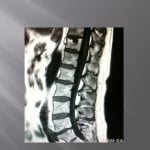

Biopsie sous guidage scanner